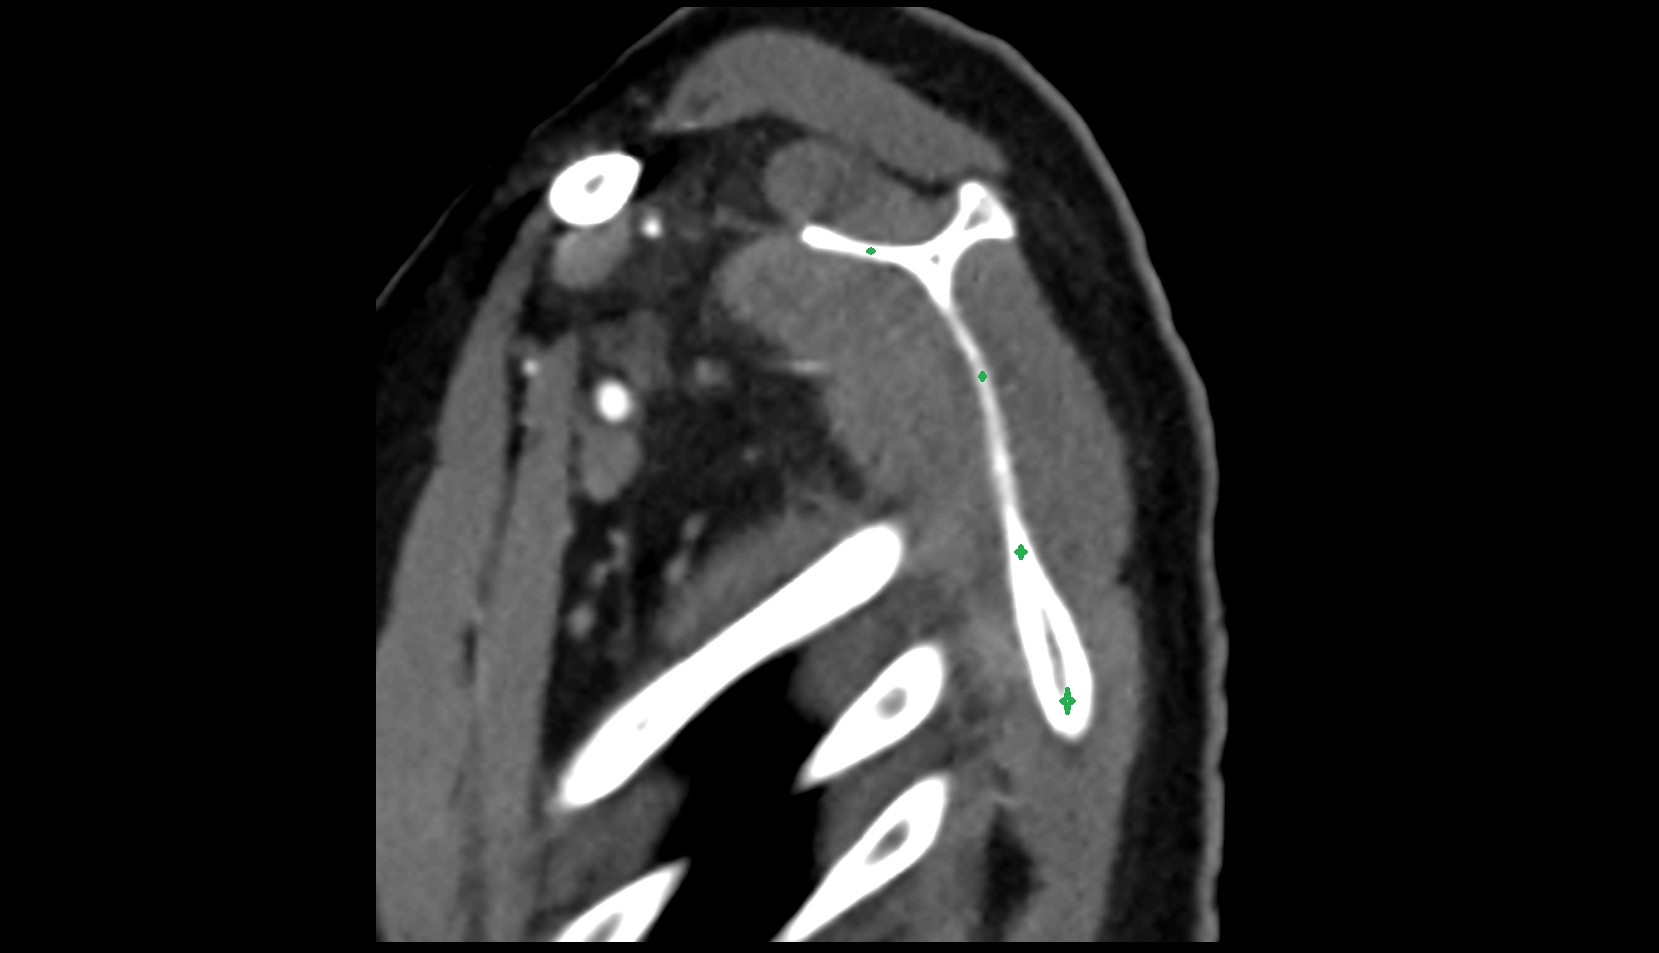

- Shoulder joint (glenohumeral joint)